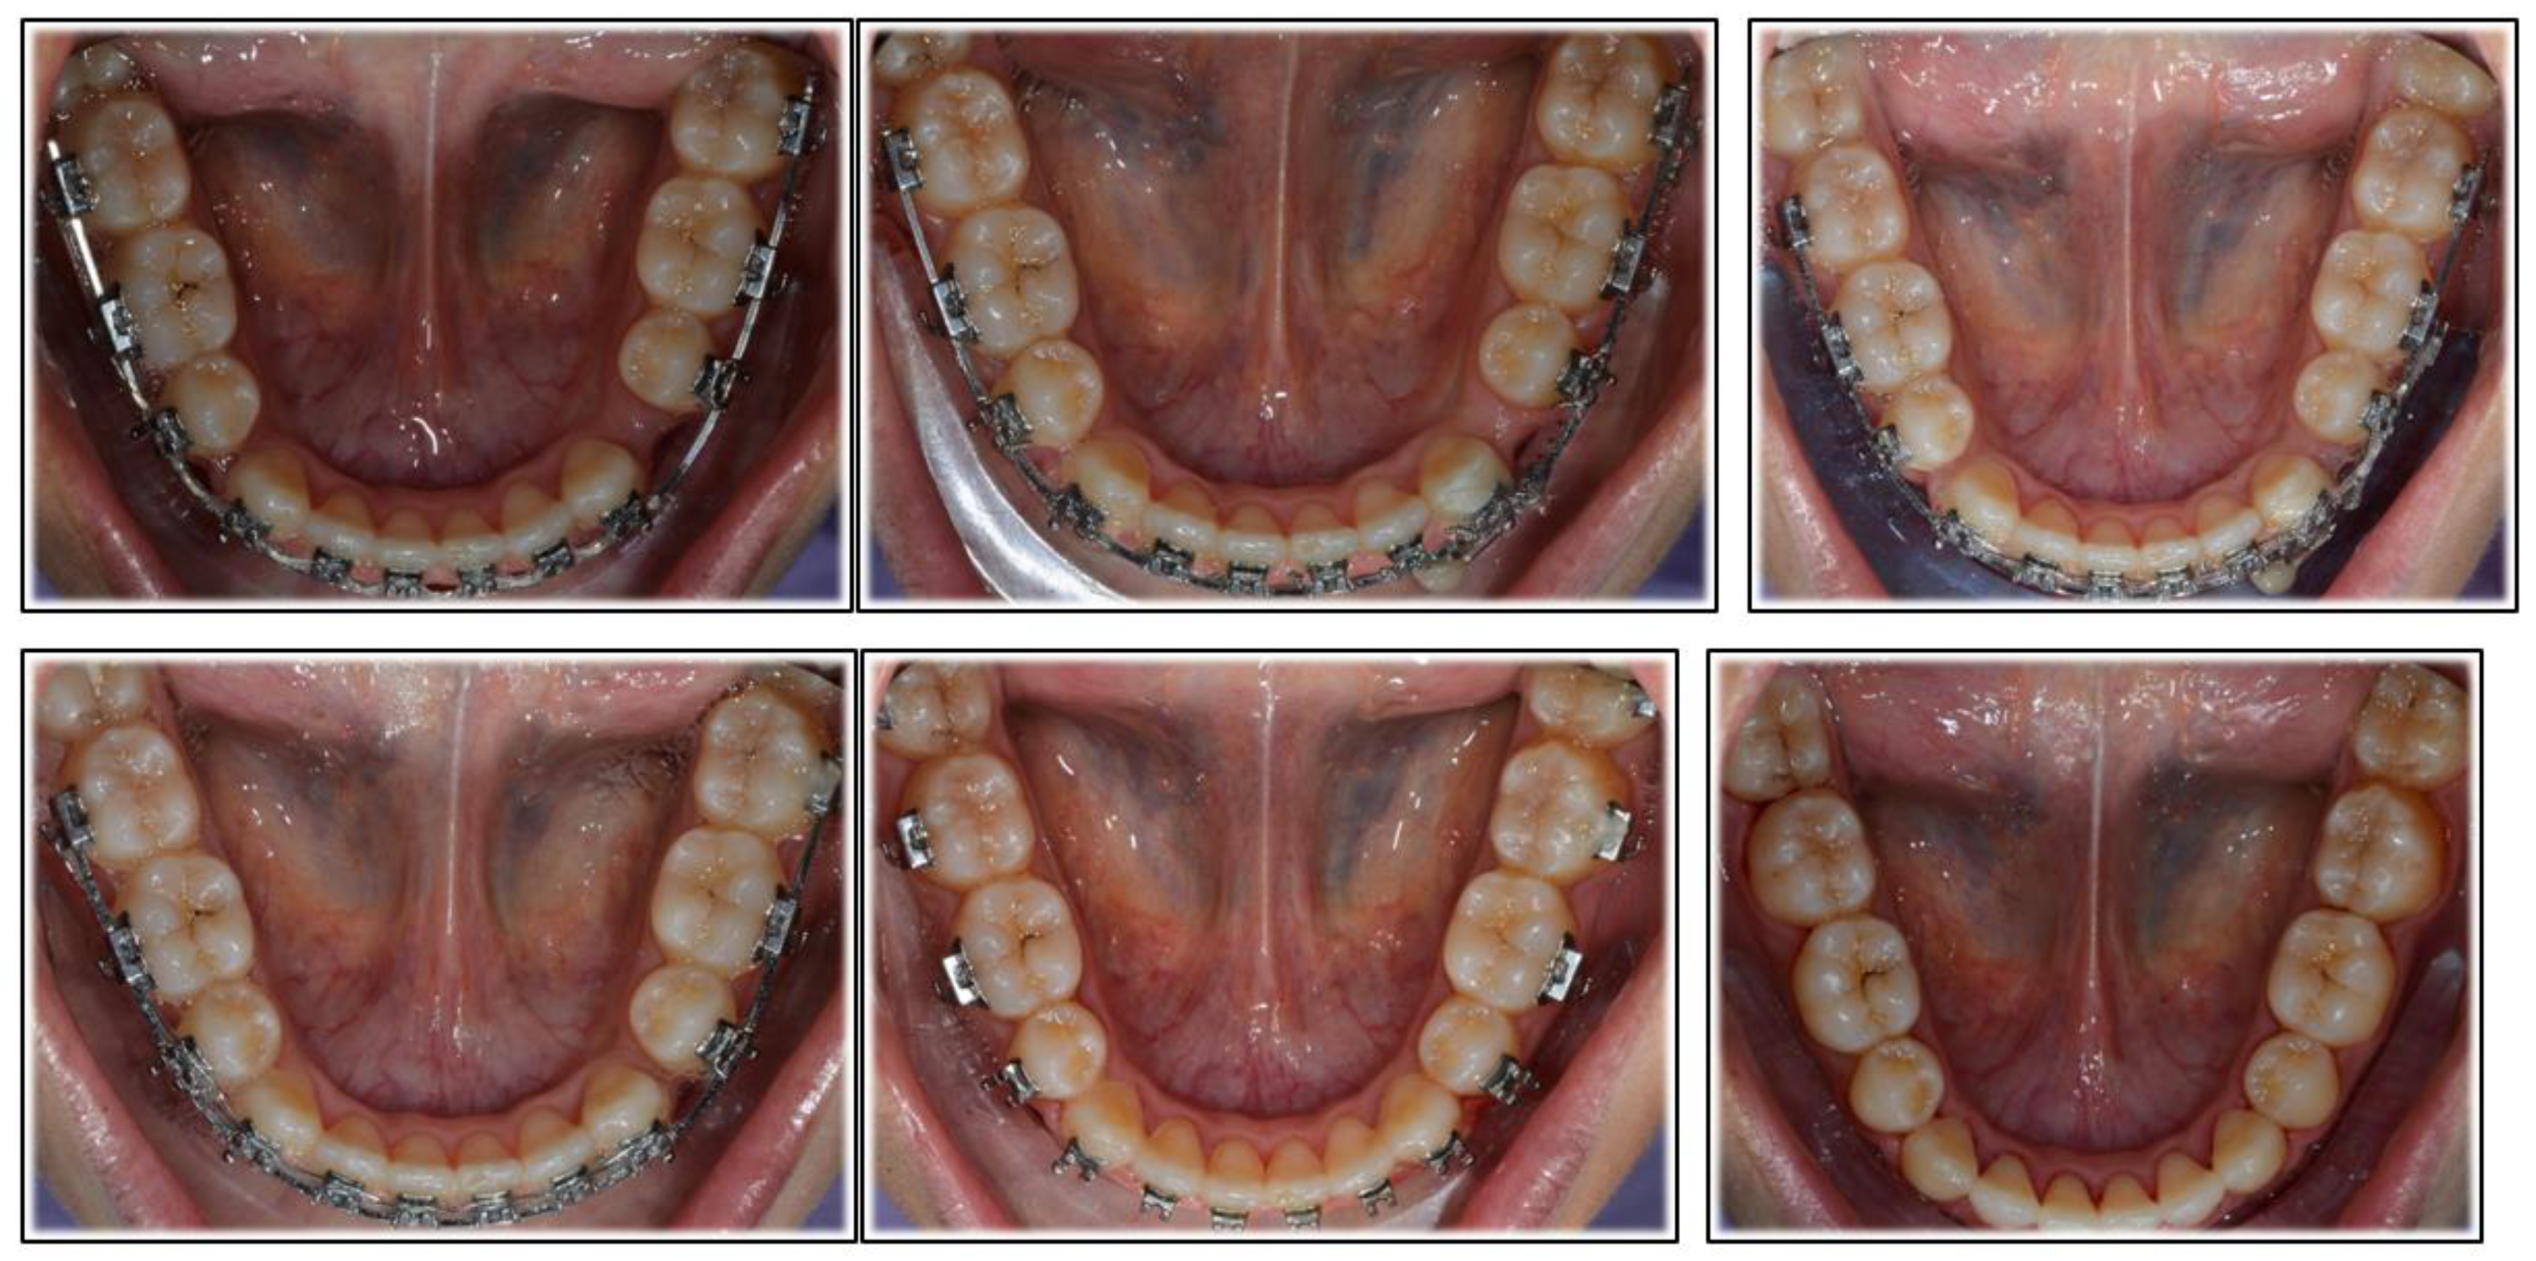

2. Case Report

2.2. Treatment Progress